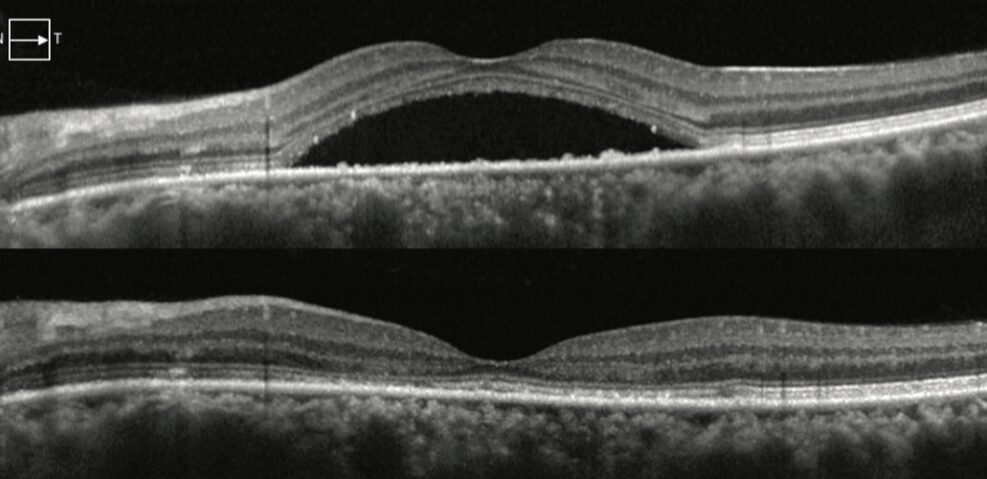

- OCT: rappresenta il gold standard diagnostico. È un esame rapido, non invasivo ed indolore che ricostruisce in 3D la retina centrale, mostrando con precisione la quantità e l’estensione del liquido sottoretinico

Nella maggior parte dei casi la prognosi della corioretinopatia sierosa centrale (CRSC) è favorevole. Oltre il 90% dei pazienti va incontro ad una risoluzione spontanea del primo episodio entro 3-6 mesi. In genere il recupero visivo è buono, spesso completo, anche se in alcuni casi possono persistere lievi disturbi come una ridotta sensibilità al contrasto.

Dopo la diagnosi di corioretinopatia sierosa centrale, il paziente deve essere seguito con OCT periodici, ogni 3 mesi nelle fasi iniziali ed ogni 6-12 mesi quando la situazione si è stabilizzata. Questi controlli permettono di monitorare il riassorbimento del liquido e di individuare subito eventuali recidive o complicanze.